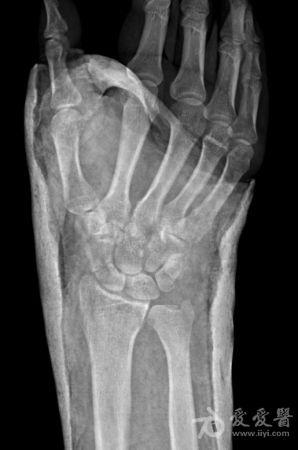

右手舟状骨骨折4个月

右手舟状骨骨折四个月,一直石膏保守治疗,拍片如下,请问,现在是手术治疗好还是继续保守治疗?